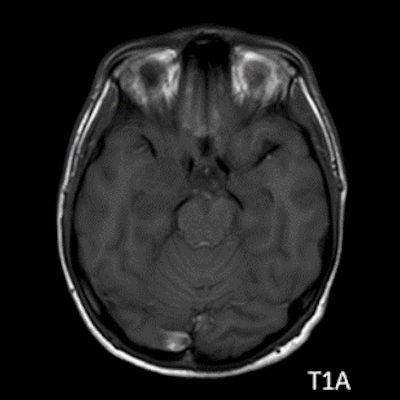

- A) Sağ temporal lob anteromedialinde silik sınırlı BT’de hipodens (ok), MRG’de T2AG ve FLAIR hiperintens (oklar), T1AG izo-hipointens (ok) sinyal özelliğinde ekspansil kitlesel lezyon izlenmektedir.

- BT: Spesifik olmayan kitle bulgularıdır. İzo-hipodens olarak izlenir. Kitle %35 oranında kalsifikasyon gösterebilir. Olgumuzda kalsifikasyon izlenmemiştir. Kemik remodelasyonu da eşlik edebilir.

- MRG: T1A serilerde solid komponent izo-hipointens, T2A serilerde genellikle hiperintens sinyalde görülür. Peritümöral T2/FLAIR hiperintens kitle ödemi oldukça nadirdir. T1 C+ görüntülerde solid komponentte değişken oranda kontrastlanma ,T2*(SWI) serilerde eğer kalsifikasyon eşlik etmekteyse buna bağlı blooming artefaktları görülebilir.